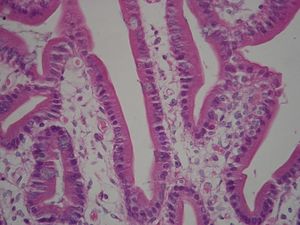

هناك عدة آلاف من الخملات الدقيقة متواجدة عند السطح القمي apical surface لخلية واحدة في الأمعاء الدقيقة للإنسان (زغابة معوية intestinal villus).

تحور الغشاء الخلوي عند السطح القمي apical surface للخلايا العمادية الطلائية Columnar Epithelium Cells الإمتصاصية ليكون ثنيات إصبعية الشكل ، تعرف بإسم "الخملات الدقيقة". وتزيد هذه الخملات الدقيقة – التي يصل طول كل منها 1-2 ميكرومتر – المساحة السطحية للغشاء ، وعادة ما تعرف بإسم "الحافة المخططة" Brush border، بينما تعرف تلك الخاصة بخلايا الأنيبيبات القريبة بالكلى Kidney proximal tubules بإسم "الحافة الفرجونية". ويحتوي لب الخملة على خييطات أكتين Actin filaments ، مرتبطة معا في حزم بروابط عرضية.